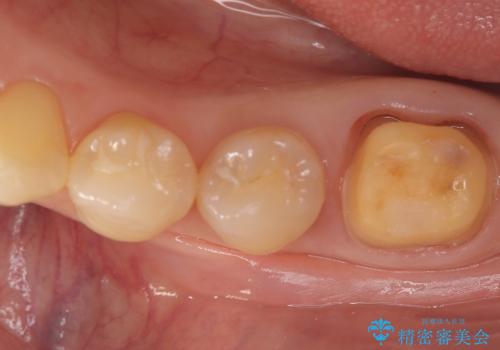

- 左下6番目(第一大臼歯)の詰め物が欠けたことを主訴にご来院されました。

診査の結果、過去に施されたCR(コンポジットレジン:プラスチックの詰め物)による修復範囲が非常に広く、咬合圧に耐えきれずに破損している状態でした。第一大臼歯は噛み合わせの要となる歯であり、最も強い力がかかるため、部分的な詰め物による再修復では再び欠けたり、残っている自分の歯まで割れてしまったりするリスクが高いと判断。歯全体を強固に保護し、機能性と耐久性を確保するために、セラミッククラウンによる修復計画を立案しました。

治療では、破損した古いレジンを除去し、セラミッククラウンを装着するための形を整えました。

広範囲にわたる欠損をセラミッククラウンで覆うことにより、咬合時の負担が歯の一部に集中するのを防ぎ、歯根の破折リスクを大幅に軽減させています。精密に作製されたセラミックは適合性に優れており、歯との段差がほとんどないため、細菌が入り込みにくい清潔な状態を作ることができます。